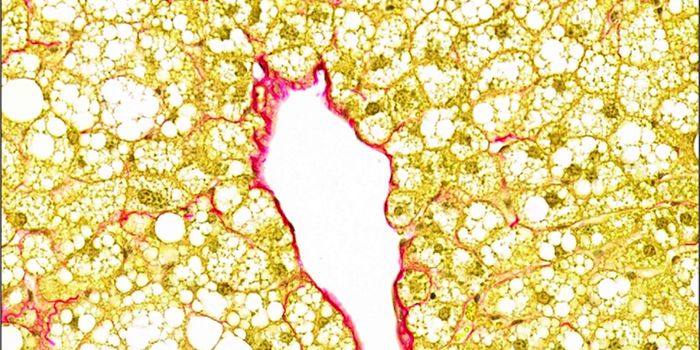

MAR 31, 2021Clinical & Molecular DXThe build-up of fat inside the liver is a worrying sign that points to the possibility of conditions such as nonalcoholi ...